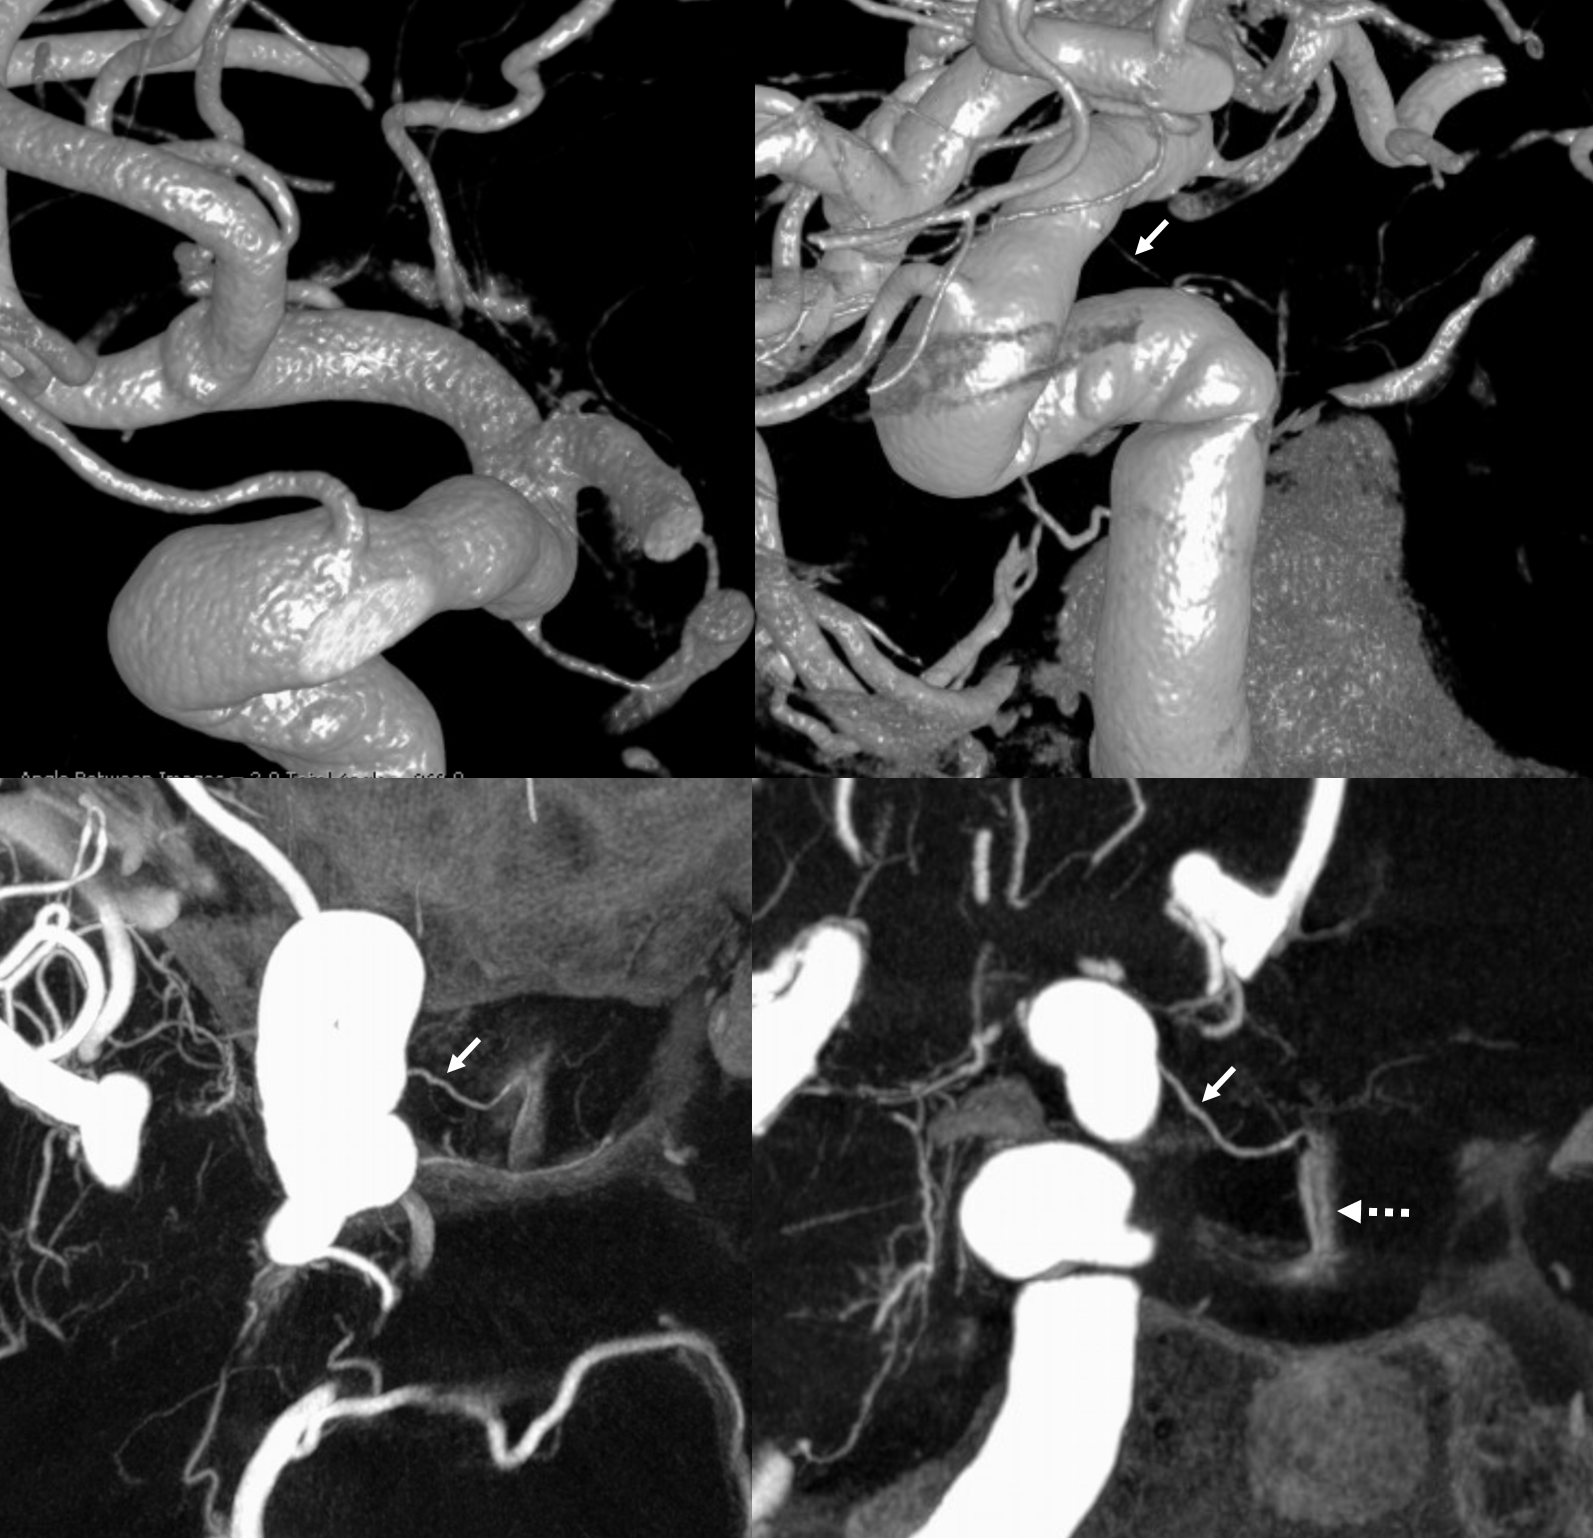

Stereos and MIPs. Both superior and inferior hypophyseals are well seen. The superior hypophyseal, despite being invisible on standard issue views, is quite large, even having two branches to the hypophysis.

Case courtesy Dr. Eytan Raz — here is a beautiful example of a very dominant superior hypophyseal artery (arrow) supplying the posterior hypophysis (arrowhead), with a correspondingly small inferior hypophyseal contribution from the MHT (dashed arrow)

Cross eye stereo

View from the back — again small inferior hypophyseal, big superior hypophyseal — balance again… See the beautiful vascular ring of the posterior pituitary — the connecting it with the contralateral side

Cross-eye stereo

MIP image shows the sella nicely — and helps prove its posterior pituitary

Pure arrowless images — easier to steal…

Of course, there is an aneurysm here — the branch point camp would point out how this larger than usual branch is a setup for aneurysmal formation. Naturally…

Below is a Volume Rendered typical arrangement — a slender (but still large by its own standards) superior hypophyseal supplies the stalk (and anterior pituitary), while inferior hypophyseal from MHT supply the posterior pituitary.